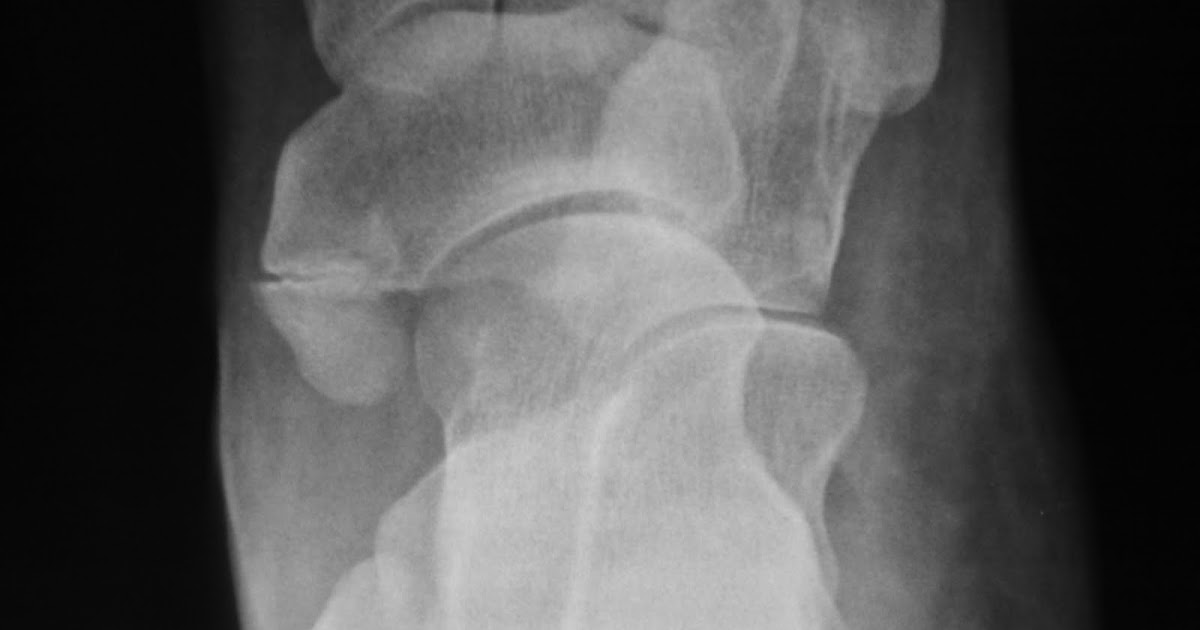

Daily Dose Fusion of accessory navicular

Daily Dose Fusion of accessory navicular Fused Accessory Navicular Radiology type 3 accessory navicular (fig. 3), which makes up the remaining 20% of cases, is a fused ossification centre, resulting in a. accessory navicular syndrome is seen with a type ii accessory navicular and is thought to relate to repetitive tension and shear stress across the cartilaginous synchondrosis as a result of pull by the powerful ptt [5,. Fused Accessory Navicular Radiology.